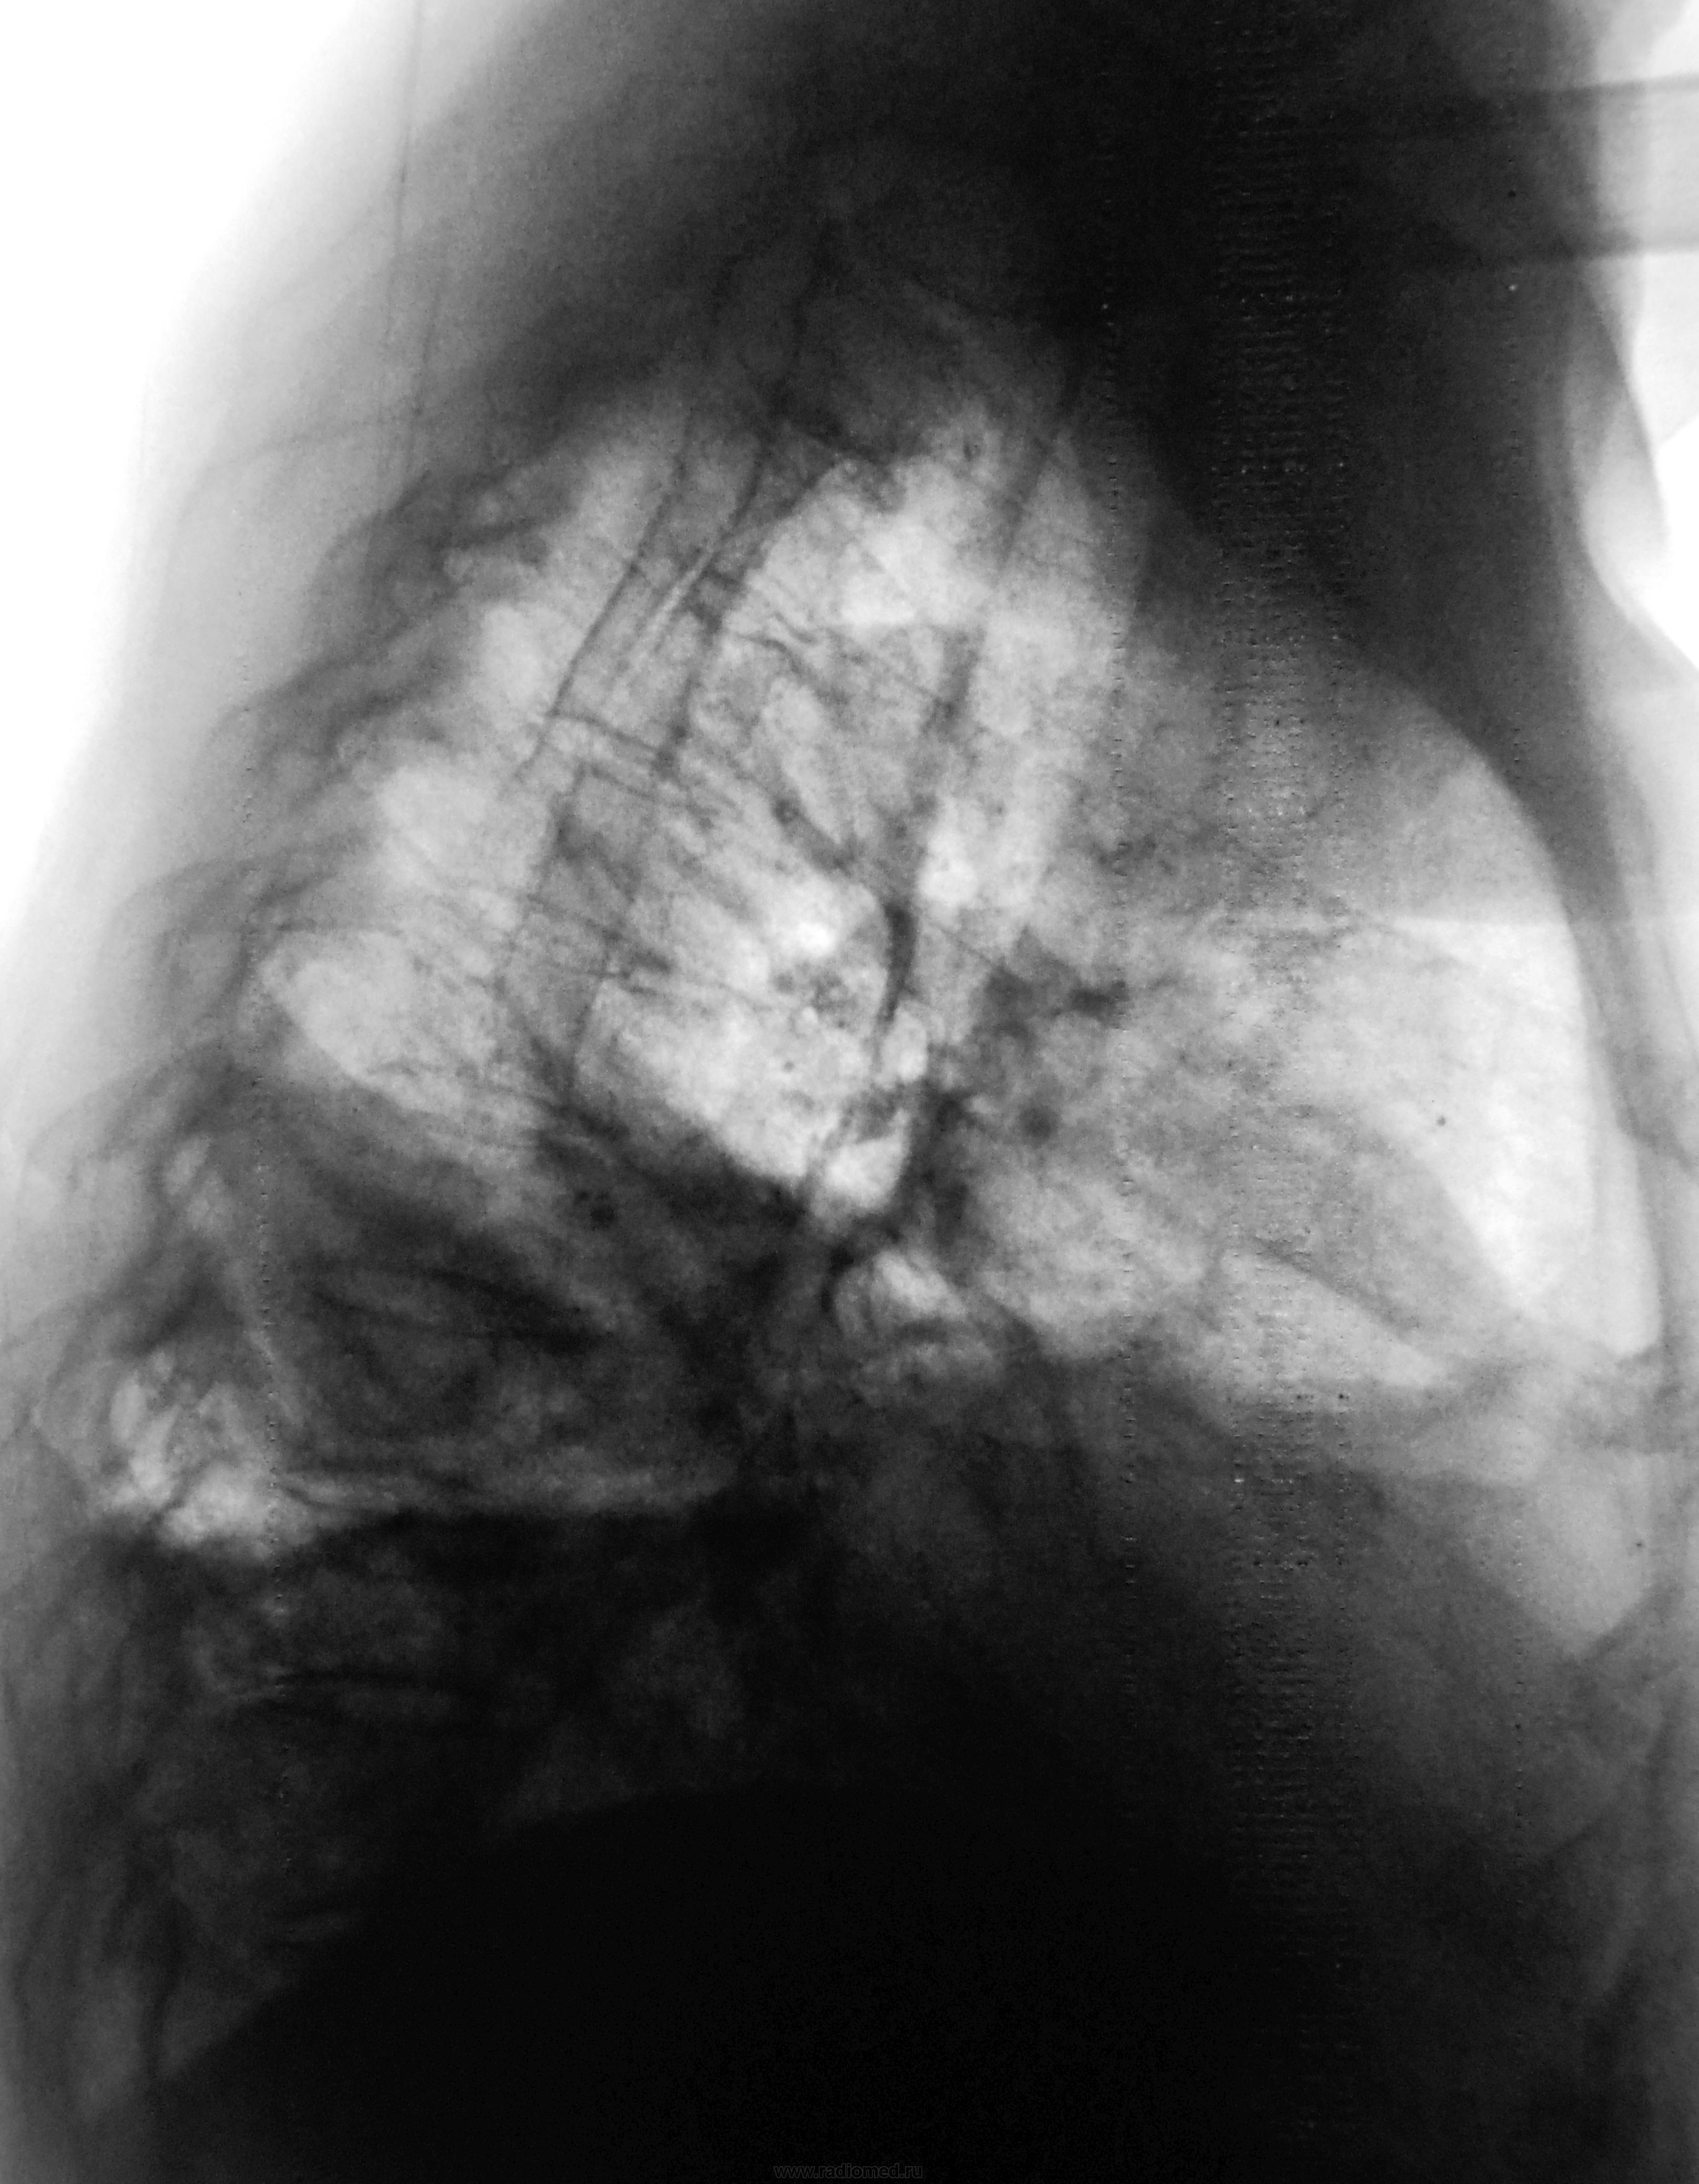

Неделю лечится в терапии, как бы по поводу сердца...

С такой эмпиемой и сердцу "несладко" придется.

это пиопневмоторакс? или только жидкость в легком? а слева на уровне дуги аорты что? нет ли там чего-нибудь посерьезней, чем инфекция?

А это в плевре, или, скорее, в легком? Эмпиема, или абсцесс?

клиники эмпиемы нет,осумкованный пневмоплеврит.

1.Пневмоплеврит (pneumopleuritis; пневмо‑ (Пневмо-) + Плеврит) экссудативный плеврит, при котором в плевральной полости наряду с экссудатом скапливается воздух; развивается при наличии бронхоплеврального свища или как осложнение искусственного пневмоторакса.

2.Эмпиема плевры (пиоторакс, гнойный плеврит) — скопление гноя в плевральной полости. Как правило, эмпиема плевры развивается в связи с инфекционным поражением лёгких (пневмонией) и часто ассоциирована с парапневмоническим выпотом. Различают три стадии эмпиемы: экссудативная, фибринозно-гнойная и организующая. При экссудативной фазе происходит накопление гноя. Фибринозно-гнойная стадия проявляется осумкованием плевральной жидкости с формированием гнойных карманов. В конечную, организующую стадию, происходит рубцевание плевральной полости, которое может привести к замуровыванию лёгкого.

Как то не очень это на пневмоплеврит смахивает. да и где соответствующий анамнез?

А клиника может быть разной, ведь эмпиема может быть и хронической.

гидропневмоторакс справа , смещение горизонтальной м/д щели кверху , левый рёберно-диафрагмальный синус уплощён - нельзя искл. небольшое кол-во жидкости и в левой плевральной полости.

Если не было пункции, то откуда воздух? Или из бронха (деструкция), или сами бактерии вырабатывают. В любом случае похоже на эмпиему.

Пневмогидроторакс осумкованный, эмпиемы клиника несоответствует. В месте темном мы оказались… Знания осветили бы наш путь. Темной стороны страшусь я.

Рак плевры? Взять жидкость на цитологию!